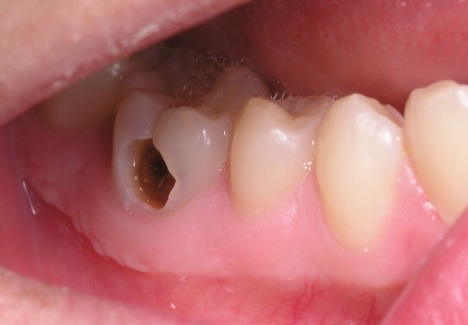

Sâu răng có thể ăn sâu xuống dưới, lâu dần lan đến cả vào tủy răng làm tủy răng viêm nhiễm khiến răng bị đau nhức. Khi vùng chóp răng bị lây lan viêm nhiễm của tủy sẽ gây nhiễm trùng. Lúc này răng lung lay, đau lại, lợi sưng to ở cạnh răng bị sâu vỡ, tạo thành ổ abscess chóp răng.

Sâu răng lan dần xuống dưới